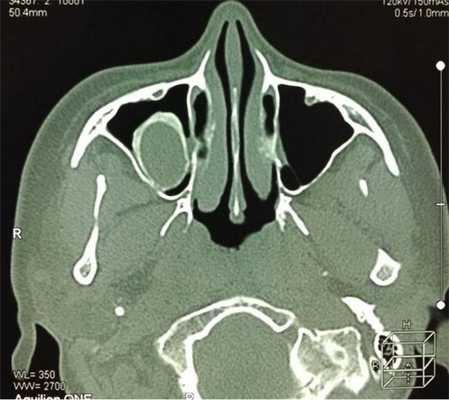

На снимке концентрическая воспалительная гипертрофия (указана стрелками) слизистой оболочки гайморовых пазух

Концентрическая воспалительная гипертрофия ячеек решетчатой кости (указана стрелками)